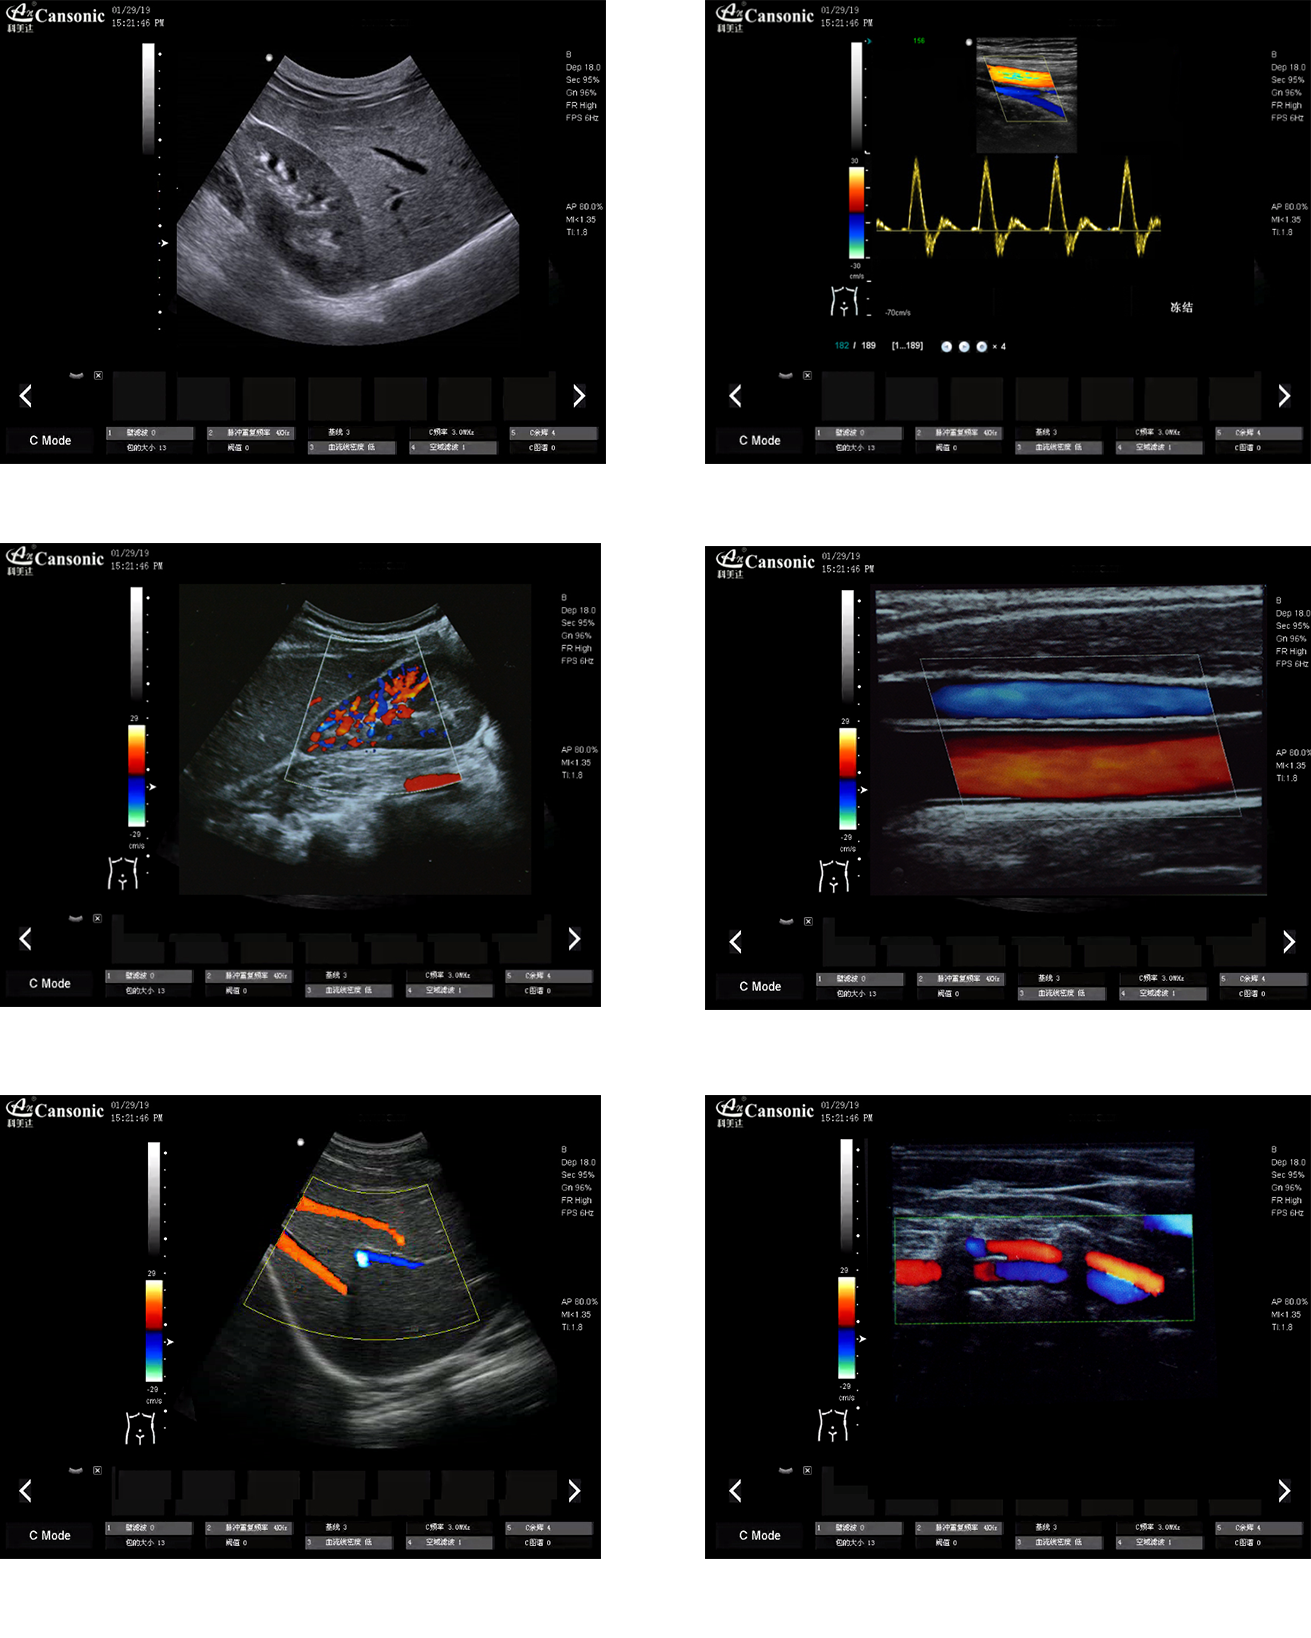

科美達K22圖像實例